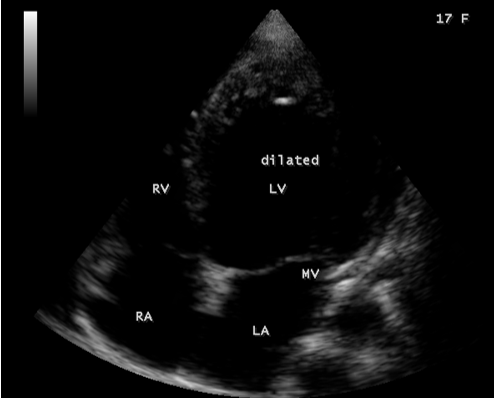

Figure 12: Apical view showing the dilated left ventricle and a normal left atrium in a 17-year old female in acute severe aortic regurgitation.

Since the patient had a bicuspid aortic valve as shown in Figure 9 and a history of rheumatic fever during childhood, rheumatic inflammation occurred on the aortic valve and harboured the infective vegetation through the vascular access during the treatment of febrile episodes. Patients with infective endocarditis are at risk of developing acute aortic regurgitation and the ECG can appear normal as in Figure 1 and the chest X-ray usually shows pulmonary edema with normal heart size. A dilated left ventricular cavity with a normal left atrium as in Figure 12 indicates that the volume overload on the left ventricle resulted a compensatory mechanism to maintain an adequate forward stroke volume by accomodating a large regurgitant fraction without an increase in end-diastolic pressure. The heart rate appeared normal (87 bpm) as the result of this compensation. Even though the aortic regurgitation is acute as in Figure 10 which showed a steep deceleration slope with a narrow width of regurgitant jet due to endocarditic lesion of aortic valve (endocarditic regurgitation). It is compensated in this patient and showed a lesser degree of decompensation as moderate LV dysfunction with an ejection fraction of 42% as in Figure 13, necessitating elective aortic valve replacement along with removal of vegetations with a mechanical prosthetic valve. Anticoagulation with warfarin to maintain the INR (international normailised ratio) between 2 to 3 is indicated after the clearance of active stage of endocarditis with antibiotic therapy and surgery.